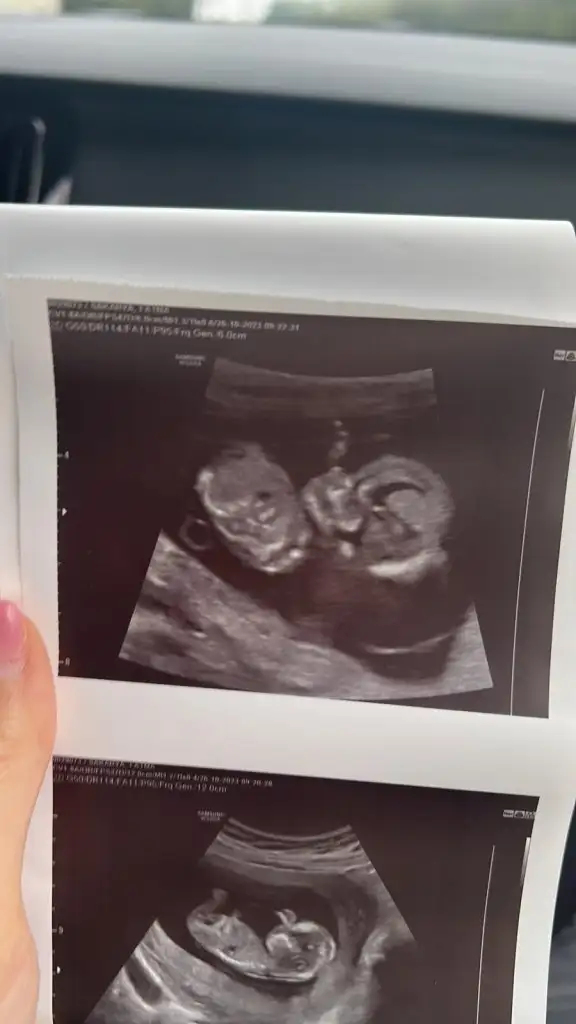

12+1 tahmin yapabilir misjniz

Eklentiler

• IMG_3396.webp

31,6 KB · Görüntüleme: 106